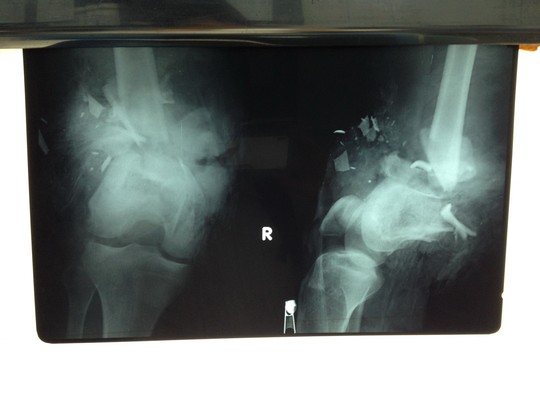

Trước đó, anh Th. nhập viện cấp cứu trong tình trạng đùi gần đứt lìa, chỉ còn dính lại một vạt da, dập nát cơ và xương. Các bác sĩ đã xử trí cấp cứu, cắt lọc bỏ các cơ hoại tử, bỏ xương đã bị dập nát…, sau đó tiến hành nối lại các mạch máu, dây thần kinh và dây chằng, đồng thời ghép lại da cứu chân bệnh nhân. Đến ngày 2-4, các dấu hiệu cho thấy chân phải của Th. được cứu sống.

Các bác sĩ chạy đua thời gian nối ráp hàng lọat bộ phận cơ, gân, dây thần kinh... để cứu chân cho anh Th.